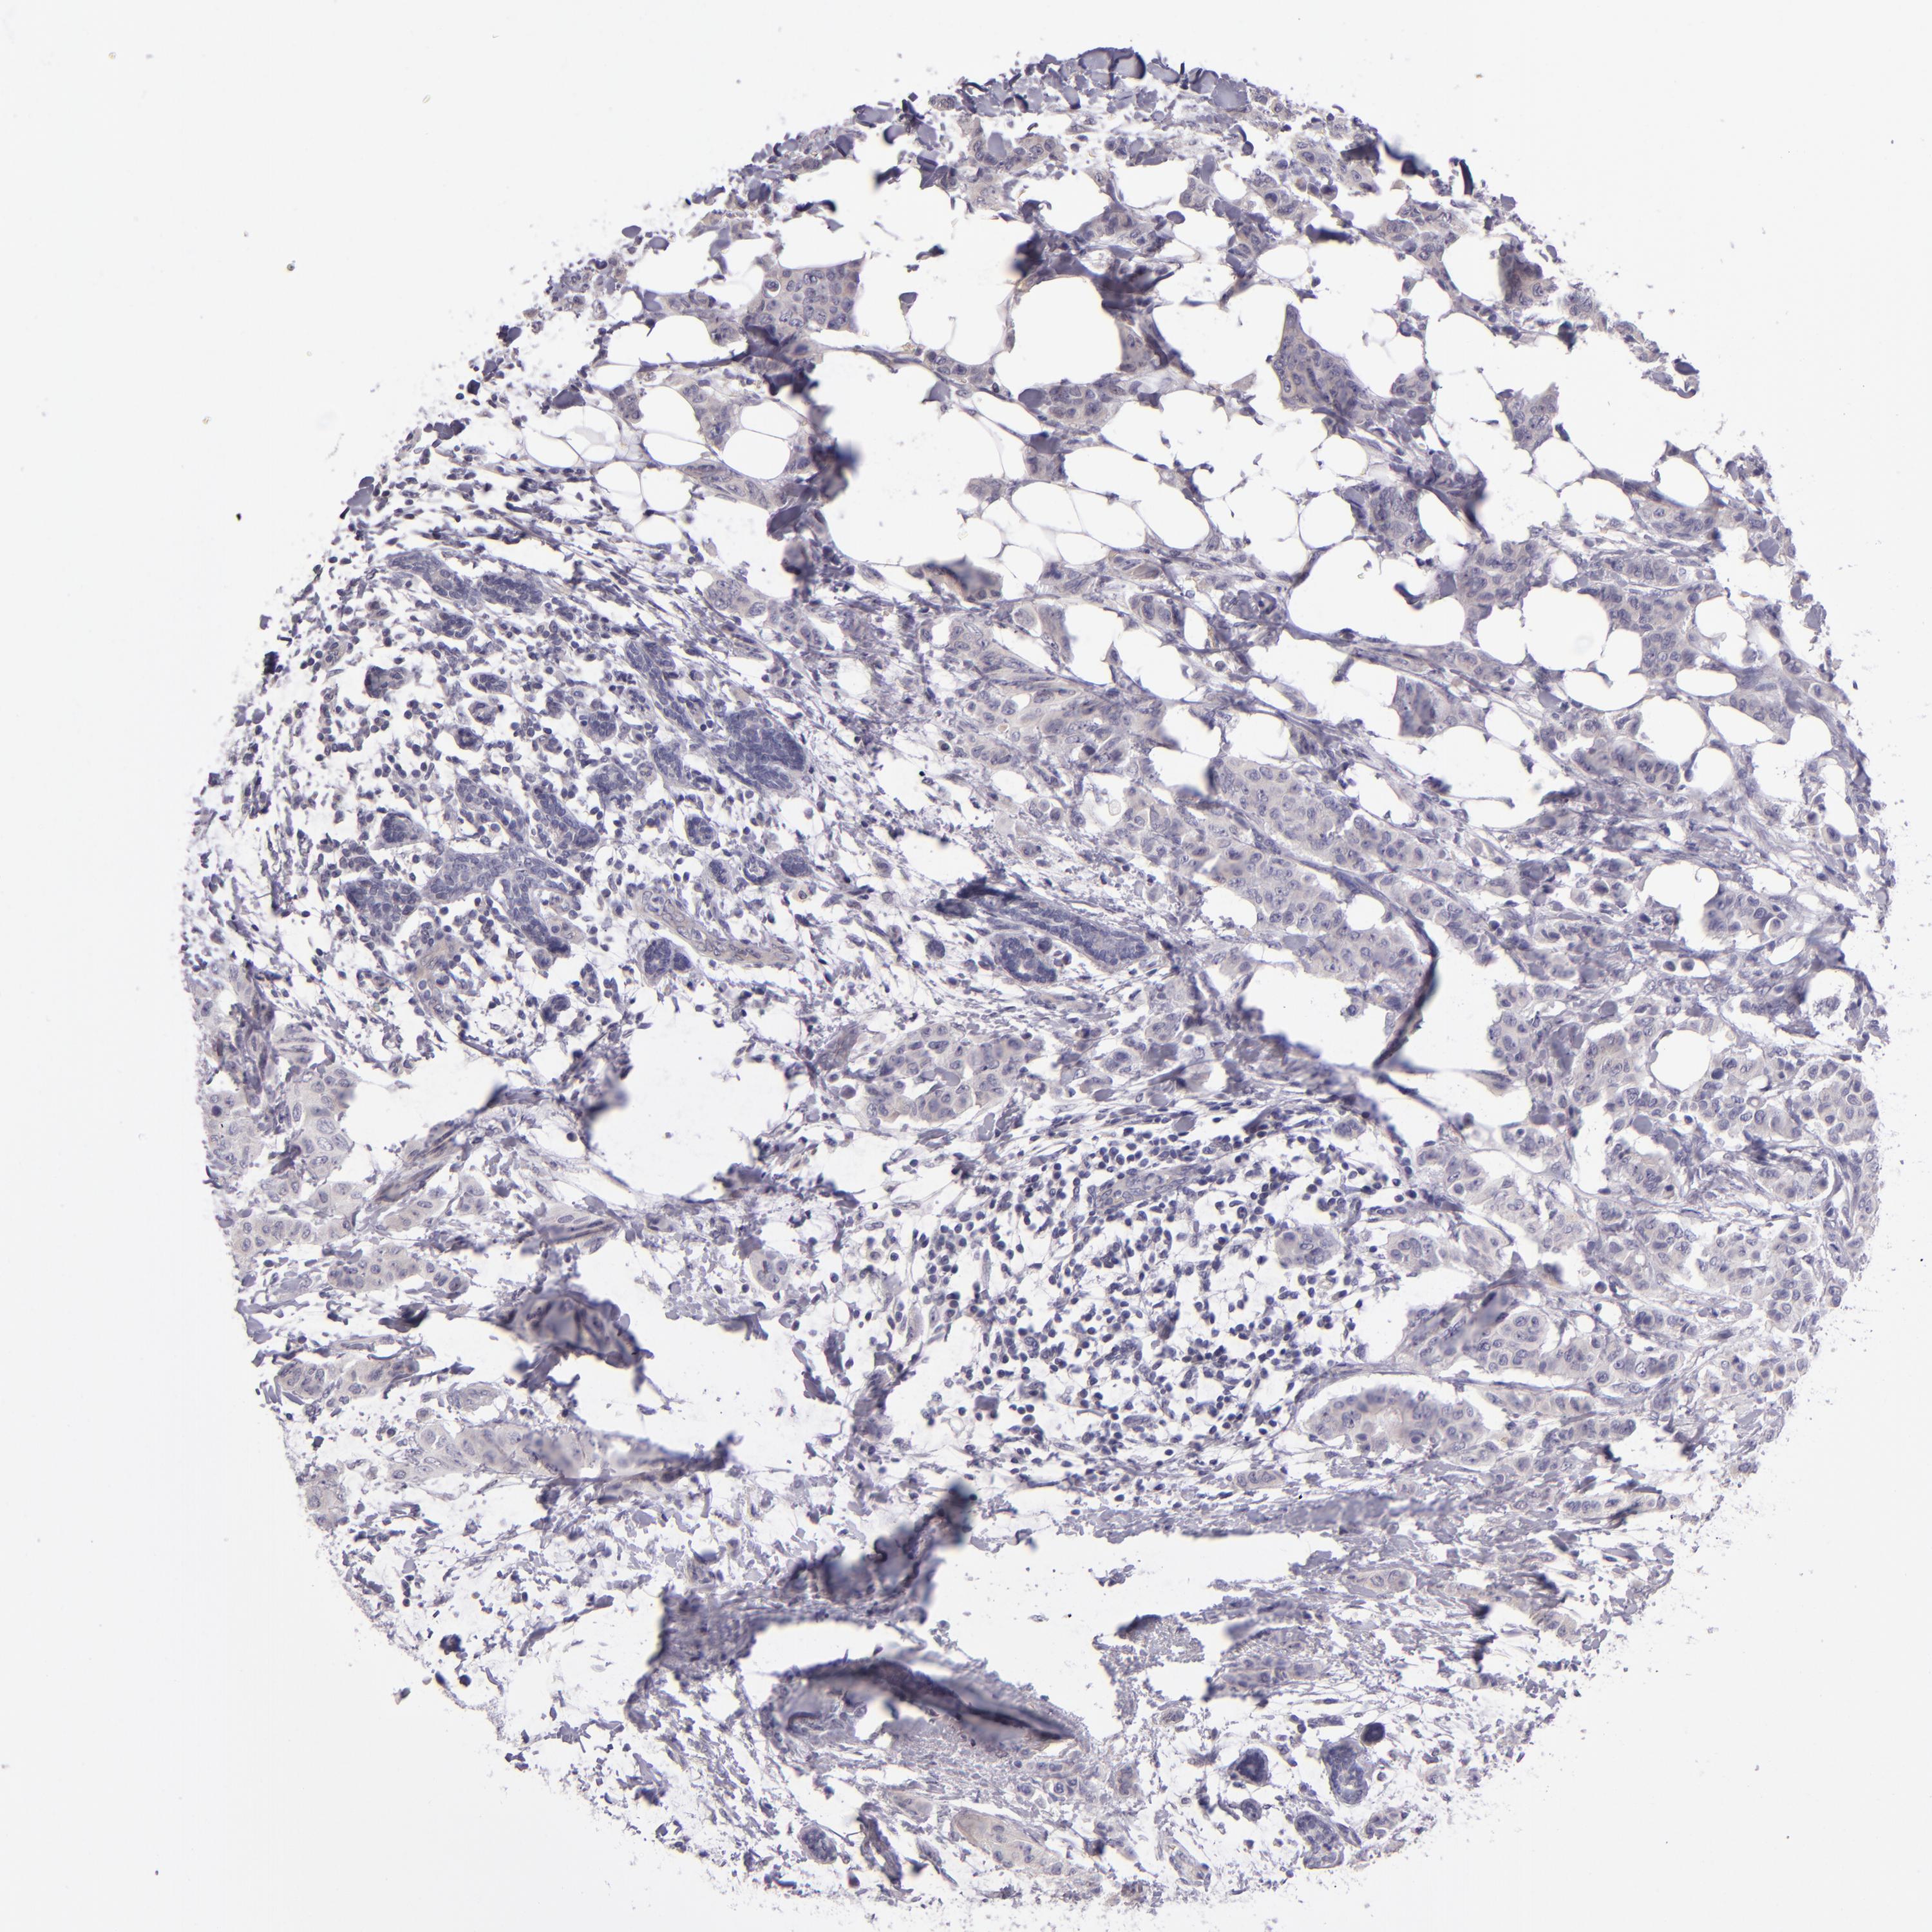

CANCER BREAST CANCER Show tissue menu

Breast cancer

Human cancer

SNCB is not prognostic in Breast Invasive Carcinoma (TCGA)